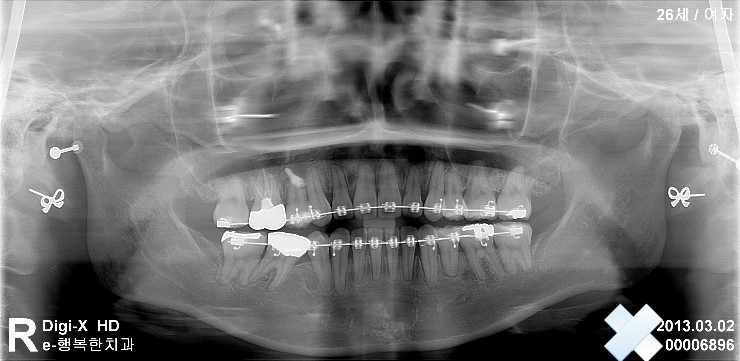

안녕하세요 지금 교정중인 사람 입니다 발치교정중이구요 아래 사진은 제가 근무하는 병원에서 찍은 사진 입니다. 첫 사진은 교정후 3-4개월 정도 지난 후 이구요 제가 궁금한건 제가 14번 발치를 했는데요 원래는 15...